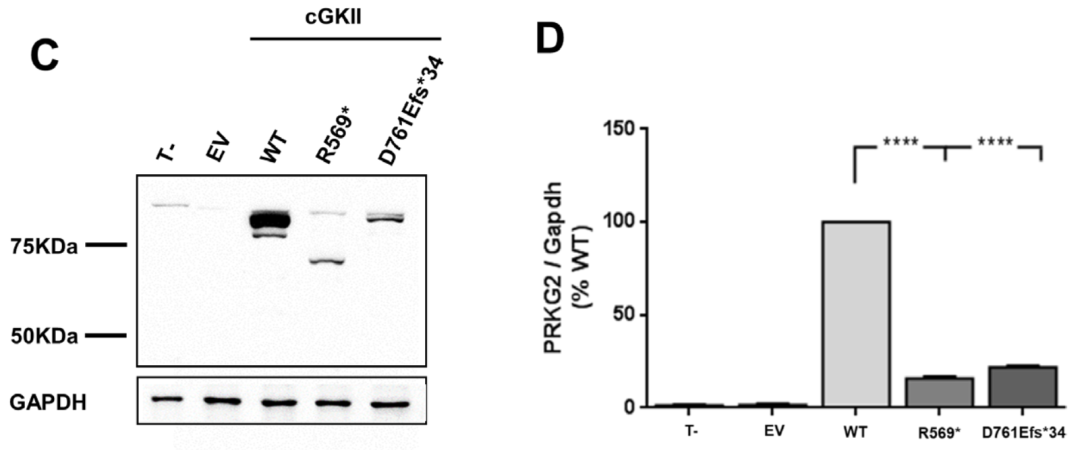

为了从功能上证实新发现的p.Asp761Glufs*34变异的致病性,我们首先用Western blot分析了cGKII的表达。以先前鉴定的p.Arg569*突变作为阳性对照,在这两个突变中,cGKII被检测到的大小与预测的大小一致,尽管与野生型相比,cGKII的水平显著降低 (≥80%)。接下来,我们通过分析p.Asp761Glufs*34突变体诱导Raf-1在Ser-43和ERK1/2磷酸化的能力,评估了它是否能够抑制FGF2诱导的MAPK通路。结果显示,p.Asp761Glufs*34突变体未能在Ser-43处磷酸化Raf-1,因此降低了FGF2诱导的ERK1/2磷酸化,这与p.Arg569*变体的结果相似。

PRKG2变异对cGKII蛋白水平/MAPK通路调控的影响